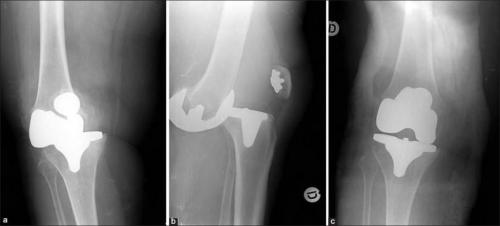

Реабилитация после эндопротезирования имеет первостепенное значение для обеспечения безболезненного функционирования сустава и улучшения качества жизни пациента. Операция попоказана для лечения болезненных и инвалидизирующих патологий, вызванных различными формами, тяжелыми травмами. Хирургом-ортопедом выполняется полная или частичная замена износившегося суставного соединения на его анатомически точную копию.

Искусственный имплантат состоит из металлических и пластиковых элементов, абсолютно безопасных для организма. Чтобы заново научить прооперированную конечность двигаться правильно, расширить диапазон доступных движений, требуются массажи, посещение физиотерапевтического кабинета, выполнение.

Такое может случиться, если очень торопиться. Это вывих коленного импланта.